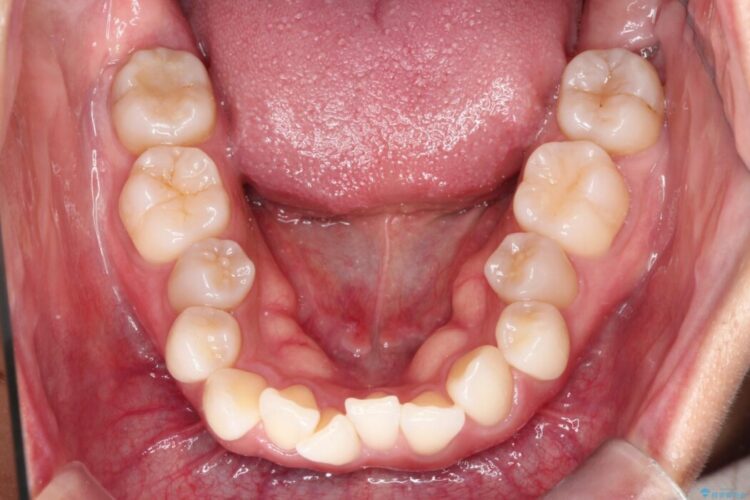

上下のガタつきと、右上の奥歯が外側に飛び出して上下が正しく噛み合わないシザーズバイトの改善のためにご来院された患者様です。

矯正検査の結果、右上7番が頬側に大きくズレており、うまくかみ合っていない状態でした。